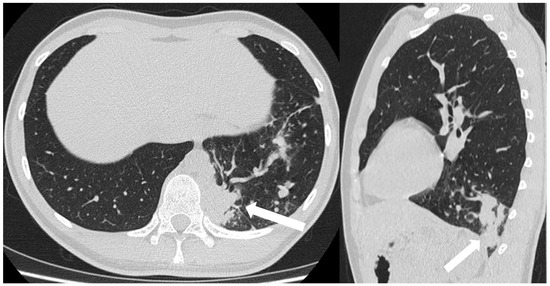

3.4.4. Congenital Bronchial Atresia

3.4.5. Bronchogenic Cysts